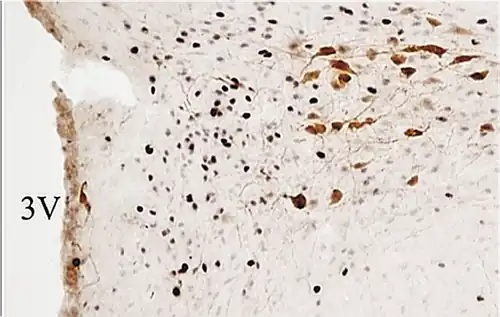

PaMP= parvocelular medial;

PaLM=magnocelular lateral.

3V= tercer ventrículo.

Neuronas magnocelulares de vasopresina (en rojo) dentro del núcleo SupraOptico.

OX= quiasma óptico. Microscopía confocal, inmunofluorescencia.